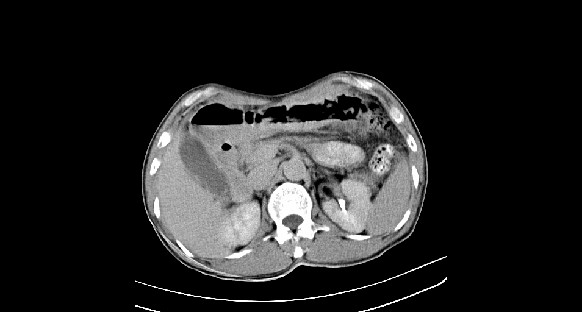

男性,70岁,体检b超发现左肾占位,请各位战友发表一下观点

左肾有两个病灶,且较大的病灶内可见点状钙化灶,增强扫描边缘也是呈渐进性强化,中央部分未见明显强化

肾癌较肾aml可能大,建议mri,若t2明显高信号者则肾癌基本诊断明确。